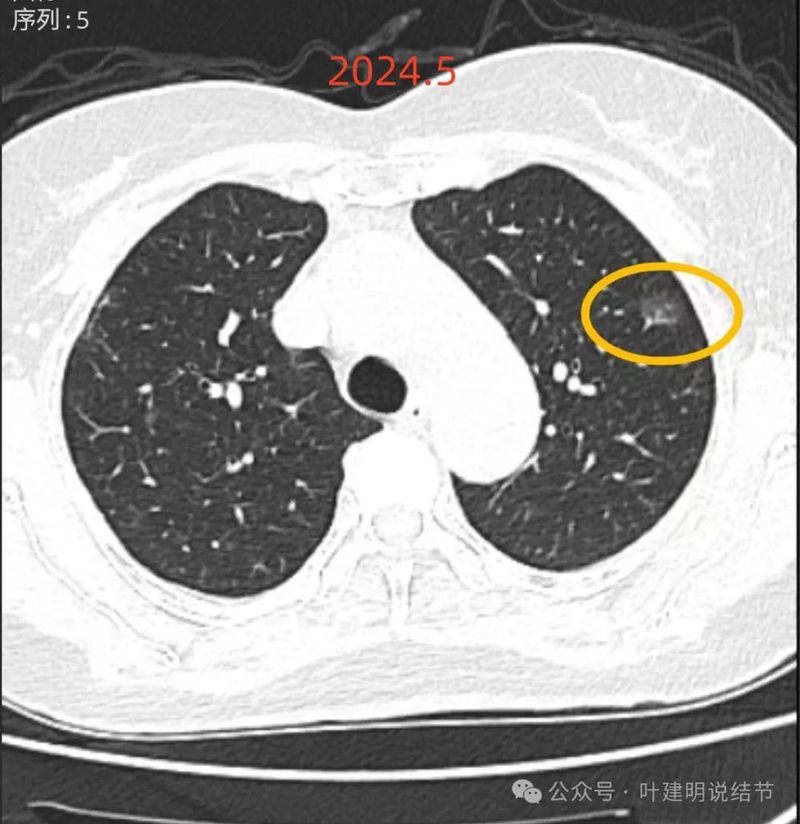

再看2024年5月时的影像:

病灶5:左上叶磨玻璃结节,有血管贴边以及小分支进入病灶内,边缘有毛刺样征,整体轮廓较清,考虑原位癌或微浸润性腺癌可能性较大;

病灶6:左上叶小磨玻璃结节,与病灶3相仿,考虑原位癌可不典型增生可能性大;

两肺多发磨玻璃结节,部分是混合密度。主病灶是红色这处在左上叶的,对比2021年有明显增大进展,考虑是浸润性腺癌可能性大,或者微浸润性腺癌;粉色的考虑原位癌可能性大;橘色的考虑不典型增生可能性大;黄色的考虑肺泡上皮增生可能性大;紫色的考虑微浸润性腺癌可能性大;绿色的考虑良性的可能性大;蓝色的考虑浸润性腺癌或者微浸润性腺癌;黑色的是2021年的时候比较明显的几处病灶。总体对比来看红色的范围增大比较明显,实性成分也有增加;蓝色的密度增加比较明显。首先考虑是多原发早期肺癌。个人觉得继续随访存在一定风险,当然由于病灶太多,也不是说都靠外科手术能够解决问题的,但是主要的有风险的病灶如果能够手术还是需要手术先解决,其他次要的病灶后续再考虑消融或者其他治疗。我的想法是先做右肺下叶背段切除(紫色,考虑微浸润或浸润)加上叶楔形切除(蓝色),下叶粉色的也可楔切或不切;之后看恢复情况过三个月左右再做左肺上叶切除。其余病灶后续如果随访进展考虑消融控制。意见供参考!为何先建议做右侧:先做右侧是因为右侧切得少,到时候再切左侧的时候,单肺通气更能耐受。如果先做左侧,下次做右侧时,左下叶单肺通气不太能耐受些。而且蓝色这处密度增加明显,又贴着胸膜,它的风险相对来说也较高,或许比左上红色的还高点。所以先做右侧。若非转移,靶向药个人不太建议吃,又不是晚期,是多原发早期肺癌可能性大呀。